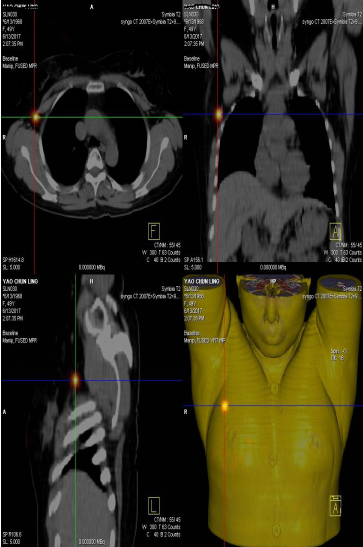

前哨淋巴結(jié)顯像技術(shù)一般在腫瘤附近注射放射性核素標(biāo)記特殊藥物,這種藥物會被前哨淋巴結(jié)攝取,存在于前哨淋巴結(jié)中。24小時之內(nèi)都可用SPECT-CT進行前哨淋巴結(jié)顯像檢查。

找到幾個淋巴結(jié)沒有明確的限制,淋巴結(jié)核素計數(shù)小于第一個SLN計數(shù)的10%就不再是前哨淋巴結(jié)了。

患者李女士,發(fā)現(xiàn)右側(cè)乳腺腫物,來我院就診,行乳腺腫物局部擴大切除術(shù),術(shù)后病理回報:右乳腺浸潤性導(dǎo)管癌III級,伴原位癌。擬行右乳腺癌切除術(shù),提檢前哨淋巴結(jié)顯像檢查,明確有無淋巴結(jié)轉(zhuǎn)移。